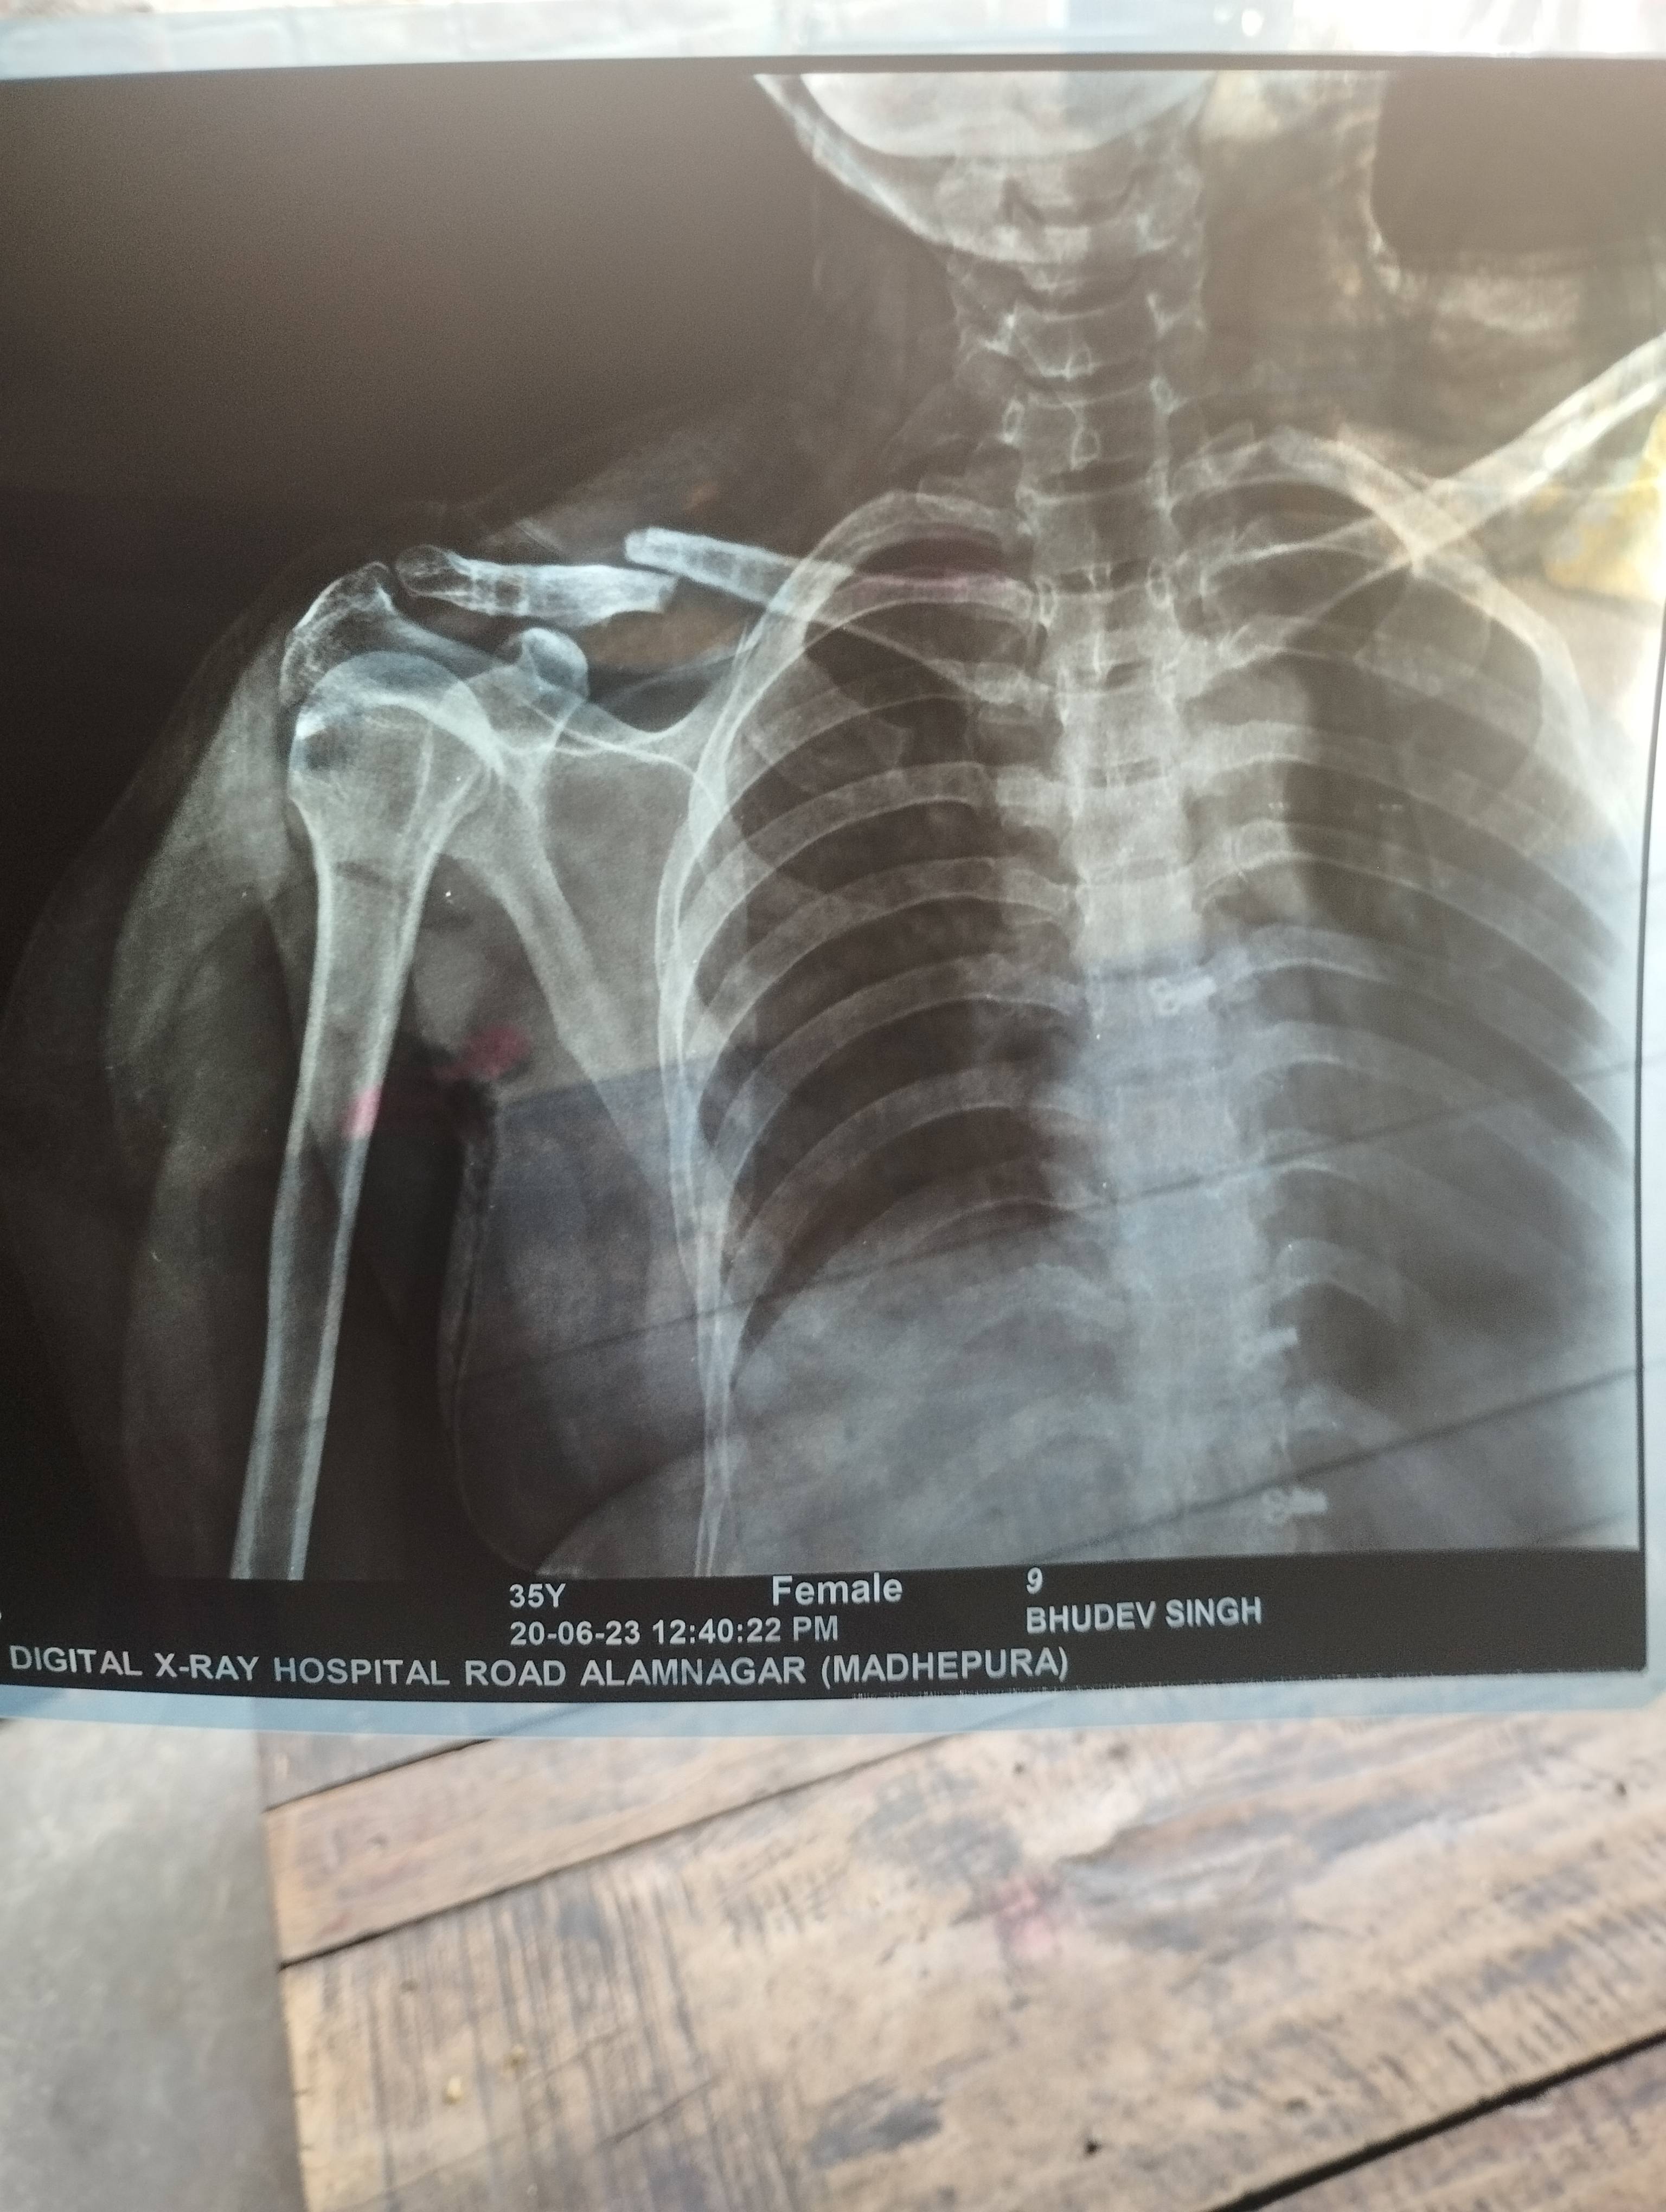

Sir i had got some fracture on hand and docs operate me on k-wire surgery on 14/06/23. Would you please suggest me for minimum how much time I'll remove those plaster and k wiring. As I have recently recruited for new job and I have to join it urgently

Reena Devi gram Mehandipur post mahmuda alamnagar Jila Madhepura